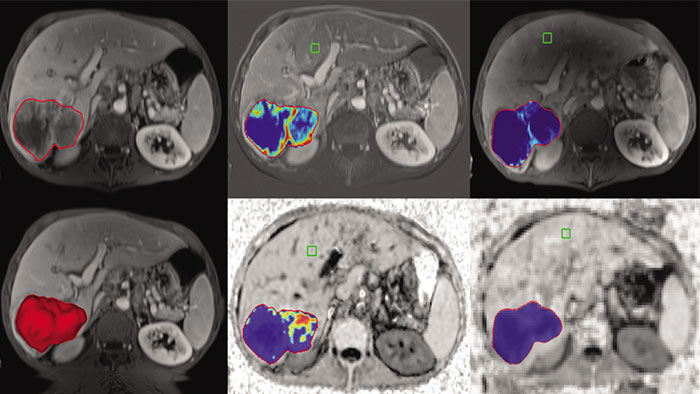

Semi-automatic tumor quantification

This semi-automated 3D (Volumetric) tumor response assessment tool, based on EASL (European Association for the Study of the Liver) criteria incorporates functional information from contrast-enhanced scans.

Computed diffusion weighted images at a b-value of choice

The application is intended to view, process and analyze MRI Diffusion Weighted Images. It calculates and displays cDWI at a

b-value of choice (from 0 to 5,000 s/mm2) and provides advanced supportive analysis and visualization tools of diffusion MRI images and parametric maps.